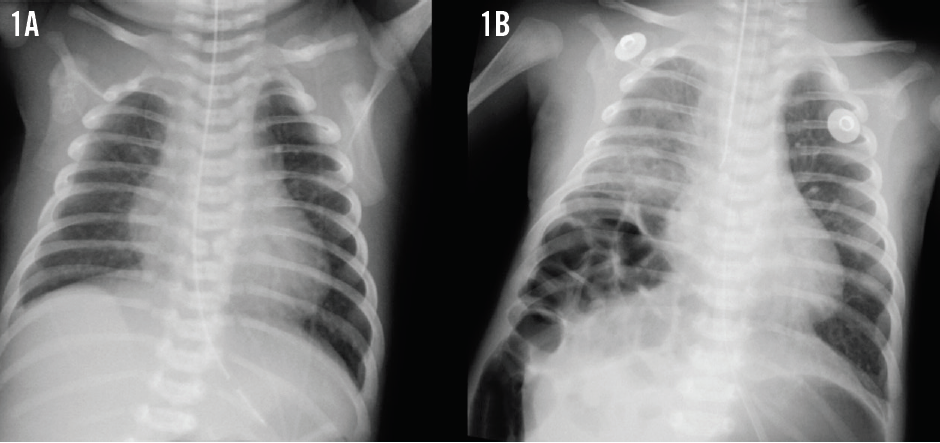

A newborn boy with a variant of unrepaired Tetralogy of Fallot had been sent for surgery for associated tracheoesophageal fistula, esophageal atresia, imperforate anus, and scrotal fistula. He also had asplenia and vertebral anomalies, but his chromosomes were normal. Postoperatively, he experienced persistent but asymptomatic gaseous bowel distension. During a routine cardiology clinic visit at 1 month of age, he developed respiratory distress unrelated to his heart defect. Pulse oximetry readings were 60% to 65% in room air, and breath sounds were diminished in the right lower quadrant. The infant was hemodynamically stable, and his pulmonary stenosis murmur was unchanged. A chest radiograph obtained 1 hour prior to the visit revealed mild cardiomegaly with increased pulmonary vascularity but no acute pulmonary disease (Figure 1A). The boy required ventilator support within hours. A repeat chest radiograph was obtained (Figure 1B).

The results of the repeat chest radiograph in the first patient showed a right-sided posterolateral delayed congenital diaphragmatic hernia that was repaired the next morning (Figure 1B). Three months later, the patient again required emergent surgery for a perforated Meckel diverticulum. At 9 month of age, he underwent uneventful Tetralogy of Fallot repair.